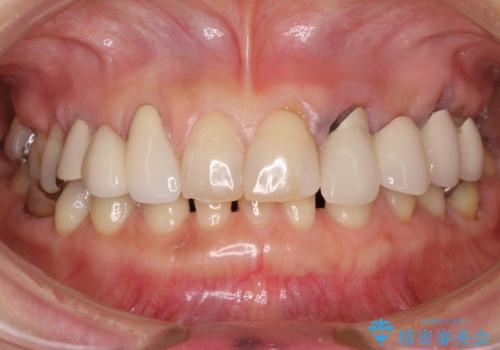

[ 金属アレルギー ] 銀歯を除去するメタルフリー治療

担当医 大元洋佑

![[ 金属アレルギー ] 銀歯を除去するメタルフリー治療の症例 治療前](https://seimitsushinbi.jp/wp/wp-content/uploads/2023/08/e81d14b5b541f23b9fcb9feb23262596-500x350.jpg?v=1692755937)